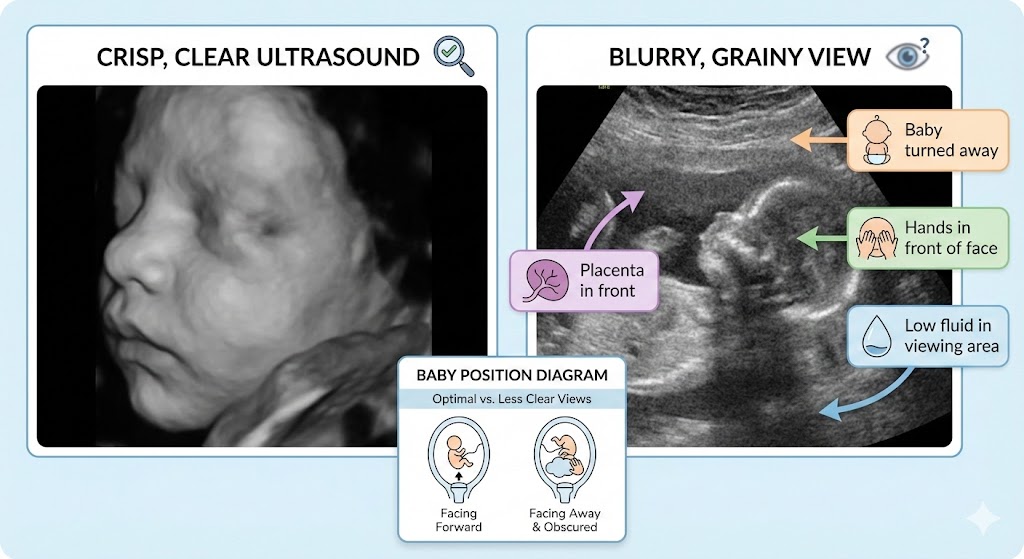

You came for the cute picture. You got a blurry gray blob that looks like a weather radar map. Annoying? Yes. Normal? Also yes most of the time.

When people say an ultrasound is unclear, they usually mean one (or more) of these:

Blurry edges (baby moved or the angle isn’t great)

Dark shadows blocking parts of the face/body (something is in the way)

Washed-out or grainy image (sound waves are weakening before they return)

Baby’s face isn’t visible (position + placenta + limbs blocking the view)

Babies don’t pose. They fold, tuck, stretch, hide, and sometimes press their face into the placenta like they’re avoiding paparazzi.

Face turned toward your back

Chin tucked into chest

Hands/feet covering face

Baby facing down (toward the spine)

Why it matters: Ultrasound needs a decent “window.” If baby is turned away or blocked, the machine can’t magically see through the obstacle.

Amniotic fluid is a big deal because it helps carry sound waves and creates contrast around the baby.

More fluid around the face/body can improve clarity

Less fluid in the viewing area can make images look flat, shadowy, or unclear

If you have an anterior placenta (placenta positioned toward the front of your uterus), it can sit between the ultrasound probe and the baby.

What that can do:

Make the image look softer or more “muted”

Add shadowing in certain areas

Sometimes block the face depending on baby’s position

Ultrasound doesn’t pass cleanly through everything. Bone blocks sound waves and creates shadows. So do certain dense or awkwardly placed structures.

Common blockers:

Hands in front of the face

Feet up by the cheeks

Umbilical cord drifting in the “camera lane”

Skull or ribs casting shadow over nearby areas

This is why you’ll sometimes see half a face and a dark patch over the rest.